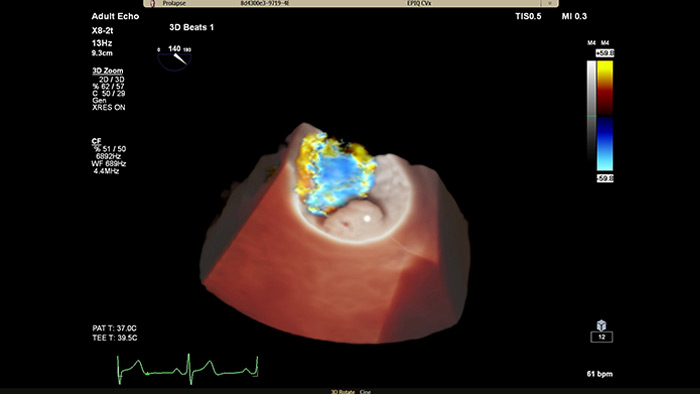

Улучшенная визуализация структур и кровотока с опцией TrueVue Color